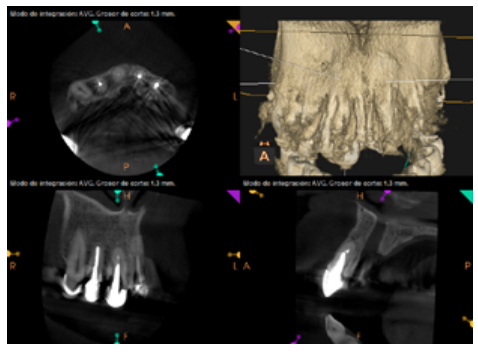

To confirm the endodontic origin and the size of the lesions, tomographic examinations were performed with a slice thickness of 75 microns using CBCT CS8100 (Carestream Dental™), in which radiolucent periapical lesions were observed at the level of 12, 11, 21 (with bicortical involvement), 25 and vestibular roots at 26 (Figures 4 to 8).

Six months later, the patient went for a check-up without any symptoms, both anteriorly and posteriorly. Periapical radiographs showed a decrease in the size of the pre-existing radiolucent periapical lesions (Figures 10 and 11). Given that the lesion on 25 remained to be treated, a control CBCT was performed where improvement at the level of 26 was verified (Figure 12), so microsurgery on 25 was scheduled.

After the microsurgery was performed on 25, the patient had no symptoms and the control tomographies at 12 months (in 25) and at 18 months in the remaining teeth showed regeneration of pre-existing radiolucent periapical lesions on all treated teeth (Figures 13 to 16).

Radiological checks were carried out at 6, 12 and 18 months using CBCT, which showed the absence of symptoms and a reversal of the chronic infection, as well as progressivity and stability in apical bone regeneration. At the level of 21, periapical radiopacity was observed, without loss of volume, and an absence of invasion of the space preserved by the surrounding soft tissue. Although some authors have used plasma rich in growth factors (PRGF) associated with Bio-Oss™ and Bio-Gide™ in cases similar to ours, we obtained adequate results without using PRGF as an additional technique13.